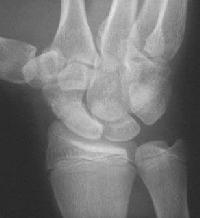

Clinical Example: Scaphoid fracture with total avascular necrosis similar to Preiser's disease

One of the problems with scaphoid fractures is ischemia of the proximal fracture fragment resulting in delayed union, nonunion or irretrievable avascular necrosis. In this case, ischemic changes involving the entire scaphoid are documented following a scaphoid fracture due to minimal trauma. This progressed with cystic changes and AVN on MRI. The patient had persistent pronounced wrist stiffness and pain. As pointed out to me by Dr. Lawrence Schneider (thanks!), this is technically not true Preiser's, for the fracture preceded the AVN.